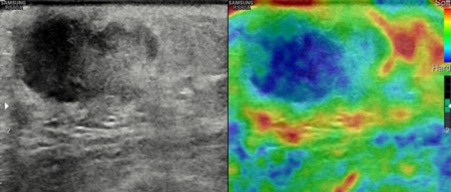

Bilateral Digital mammography , Craniocaudal (CC) and Mediolateral oblique (MLO) view revealed an irregular , high density mass with indistinct margin in retroareolar region with retracted nipple. No microcalcifications was seen. No significant axillary lymph nodes were present. Ultrasound of left breast showed an irregular, heterogeneously hypoechoic mass with indistinct margin and mild posterior acoustic enhancement, measuring about 2.5x1.9x1.3cm in retroareolar region. Internal vascularity was increased on colour doppler. On strain sonoelastogram, the mass showed increased stiffness suggestive of hard consistency. The imaging features are highly suspicious for male breast cancer and thus the mass was classified as BIRADS category 5 lesion and Ultrasound guided biopsy was advised. Patient underwent left modified radical mastectomy and final histopathological report was Invasive Lobular carcinoma. No nipple or lymphovascular invasion was identified.